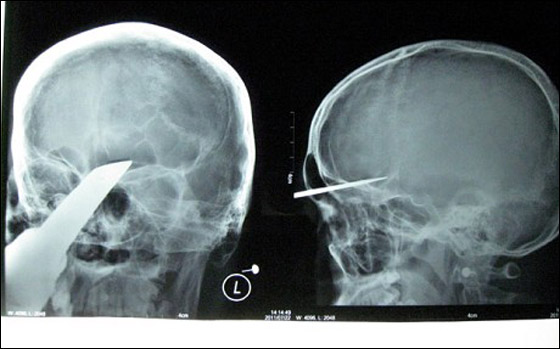

اخترق سيف جمجمة شاب صيني يدعى تشانغ بن (15 عاما)، حيث انغرس في جبينه على عمق 5 سم بينما كان يتسكع مع اصدقائه، وبعد الحادثة هرع الشاب الى المستشفى، ولكن لم يتمكن المسعفون من تقديم علاج له، وبقي الشاب صامدا حوالي 4 ساعات قبل ان ينقل الى مستشفى في تشانغشا في الصين، والتي تبعد 250 ميلا عن المستشفى الذي نقل اليه في البداية.

وقال تشانغ: "جاء ثلاثة من اصدقائي لزيارتي في المنزل، وحمل احدهم سيفا معه، وقد جلس على بعد 3-4 امتار مني، وفجأة وبدون علمي، طار السيف باتجاهي وانغرس في جبيني، وحينها شعرت بالام حادة، ورأيت كمية هائلة من الدماء تتدفق من راسي".

وفور وصول تشانغ الى المستشفى، اسرع الاطباء لادخاله الى غرفة العمليات، لاجراء جراحة عاجلة له، ولحسن الحظ، تمكنوا من ازالة السيف وذلك بعد مرور 4 ساعات على ادخاله الى غرفة العمليات. وقال الجراح الرئيسي الذي اشرف على الجراحة: "لحسن الحظ، لم يصل السيف الى الدماغ، والاعصاب، والا ستكون حالته اسوأ مما كانت عليه بكثير". ومن الجدير بالذكر ان تشانغ ما زال يتلقى العلاج، وقريبا سوف يشفى تماما.